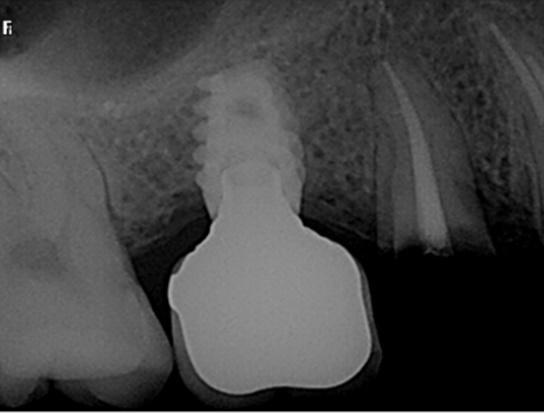

40 años acudió para la rehabilitación del sector posterior superior, pues presentaba un defecto vertical en el cuadrante superior derecho a la altura del primer molar, una altura óseorresidual de 3.5 mm y un tipo óseo III. Dadas las condiciones, se optó por la técnica de oseodensificación para la elevación del piso del seno maxilar y la preparación del lecho implantario. Entre los hallazgos descritos en los resultados se encontró una elevación sinusal de al menos 6 mm, evidenciada en las imágenes radiográficas intraoperartorias, que permitió la colocación de un implante de 5 mm de plataforma por 8 mm de longitud, ubicado 1 mm en posición subcrestal. Una tomografía

axial computarizada confirmó la situación del implante, así como la efectividad de la oseodensificación y la elevación del piso sinusal de 6 mm. la osteointegración del implante se completó sin necesidad de procedimientos quirúrgicos adicionales de mayor complejidad. Se concluye que la oseodensificación es una técnica eficaz y predecible para la osteotomía y la elevación sinusal transcrestal, favorece la estabilidad primaria del implante y constituye un procedimiento mínimamente invasivo.

Figura 2. Planeación en tomografía axial computarizada: a) vista sagital, b) vista transversal, c) vista 360°, d) reconstrucción 3D y e) ortopantomografía.

Se creó un mapeo óseo para evaluar las dimensiones de altura y anchura ósea disponibles para la colocación del implante dental y su posterior restauración protésica. El análisis reveló una cantidad reducida de tejido óseo en el piso del seno maxilar (3.61 mm), lo que condicionó la planificación del procedimiento. Para la rehabilitación implantológica, se requiere la colocación de un

implante de al menos 8 mm de altura por 5 mm de diámetro, con adecuado espacio vestíbulo-palatino e interoclusal. No obstante, luego de considerar la insuficiencia de volumen óseo en sentido vertical y el grado de neumatización del seno maxilar, se determinó que la colocación del implante mediante técnicas convencionales no era viable, por ello la necesidad de procedimientos de aumento óseo para lograr una rehabilitación adecuada (Figura 2).

Figura 3. Protocolo de fresado quirúrgico: a) fresa piloto sentido horario, b) comprobación radiográfica, c) RX pin de paralelismo, d) fresa 2.3 sentido antihorario, e) comprobación radiografía periapical de posición y elevación del piso de seno, f) fresa 3.2 a 9mm con elevación evidente, g) verificación de profundidad con sonda del kit de implantes, h) colocación de injerto de hueso NovaBone, i) vista del hueso en el lecho quirúrgico j) fresa final diámetro 4.3, k) RX de comprobación de fresa 4.3 y l) RX de implante e injerto colocados.

fresado (fresa de 4.2 mm de diámetro) dentro del sitio preparado como indica el protocolo de fresado Versah. Gracias al diseño específico de las fresas, el biomaterial fue distribuido hacia las zonas superior y lateral del sitio quirúrgico para promover una adecuada condensación ósea y facilitar la colocación del implante en una posición subcrestal de 1 mm.

Entre cada cambio de fresa, se verificó radiográficamente la dirección y profundidad del fresado. Finalmente, se completó el protocolo con el uso de la fresa de 4.2 mm de diámetro hasta alcanzar una profundidad final de 9 mm. Se obtuvieron imágenes radiográficas que evidencian la correcta colocación del injerto en la elevación lograda (ver Figura 3).

Una vez colocado el implante de la marca Adin Closefit de 5 mm de diámetro × 8 mm de largo, se lavaron profusamente la zona periferia y el interior del implante con solución fisiológica estéril. Cuando se instaló el tornillo tapa

correspondiente, se evaluó la estabilidad primaria mediante la técnica de torque de inserción y una llave dinamométrica, instrumento diseñado para medir y controlar la fuerza aplicada durante la inserción del implante. Este parámetro refleja la resistencia y rigidez de la interfase hueso-implante: a mayor torque, mayor estabilidad primaria (Figura 4).

Resultados

Se logró una elevación sinusal de 6 mm en el sitio destinado para la colocación del implante endoóseo. Se colocó injerto sintético en la zona elevada para implantar en una única sesión quirúrgica, y se obtuvo un torque final de 100 N•cm, lo que indicó una excelente estabilidad primaria. La rehabilitación protésica se realizó sin complicación alguna, mediante una corona atornillada metal-cerámica, 2 meses después de haber colocado el implante. La integridad de la restauración se mantuvo en óptimas condiciones durante el seguimiento clínico a 5 años de la rehabilitación.

Se observaron excelentes condiciones clínicas y radiológicas, entre las que destacan: reducción de la cresta ósea menor a 1 milímetro y ausencia

de movilidad y sintomatología. La restauración es plenamente funcional y estética; la paciente refiere estar muy satisfecha, lo cual representa un éxito, con base en artículos referentes a los criterios de éxito en implantes dentales.

La Figura 6 presenta una comparación entre el estado previo a la colocación del implante y el estado actual. Se observa que, a pesar de un notable deterioro en los dientes naturales adyacentes, existe integración y funcionalidad satisfactorias, además se evidencia el aumento de volumen óseo obtenido.

Figura 5. Ortopantomografía 3 meses después de colocado el implante. Se aprecia la elevación sinusal y el hueso injertado.

permitió la colocación del implante sin necesidad de recurrir a procedimientos más invasivos, lo que evidencia su utilidad en sitios con altura ósea limitada. Los hallazgos intraoperatorios y postoperatorios presentados en este artículo corroboran la eficacia de la oseodensificación, debido a que la elevación sinusal alcanzada fue de 6 mm, lo que posibilitó la colocación de un implante de dimensiones adecuadas con estabilidad primaria óptima.

Estudios previos, como los de Huwais & Meyer (2017) y Trisi et al. (2016), demuestran que esta técnica no solo aumenta la densidad ósea, sino que también contribuye a la expansión del tejido óseo y favorece la osteointegración a largo plazo.29 La capacidad de compactación ósea observada en este caso clínico es consistente con los resultados obtenidos en estudios experimentales, ya que el torque de inserción resultante de la OD y del injerto de hueso fue de 100 N·cm. Debido a que el mínimo en N·cm es de 35 para obtener una buena estabilidad primaria; se evidenció un aumento del volumen óseo notablemente visible en las radiografías del caso y en la TAC presentada.